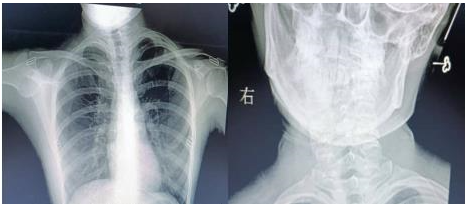

通訊員楊航報道:18歲的小唐(化名)是個笑容明媚的在校大學(xué)生,平時無論是坐著,站著,走路,脖子就不由自主的偏斜,這種情況讓小唐很困擾。多年來,小唐父母帶她去多家醫(yī)院保守治療,效果還是不理想,經(jīng)過多方打聽,慕名來到衡陽市中心醫(yī)院骨科一區(qū)求醫(yī)。錢軍副主任接診后詳細詢問病情,結(jié)合相關(guān)輔助檢查,診斷小唐(化名)是“先天性肌性斜頸”。

近日,在蘇光輝主任帶領(lǐng)下,制定完美的手術(shù)方案,與麻醉科及手術(shù)室的共同配合下,順利進行了左側(cè)胸鎖乳突肌攣縮胸骨頭+鎖骨頭切斷+胸鎖乳突肌黏連松解+切口美容縫合手術(shù)。術(shù)后經(jīng)過精心護理,患者恢復(fù)良好,患者及家屬對手術(shù)效果非常滿意,現(xiàn)已佩戴支具出院。

錢軍副主任介紹,“先天性肌性斜頸”最常見的原因是患兒出生前胎位不正,頭頸部扭曲,致頸肌肉供血發(fā)生障礙,肌肉變形、逐漸攣縮,引起頸部兩側(cè)肌肉平衡失調(diào),使頭部偏向變攣縮的一側(cè),形成頭頸側(cè)斜。